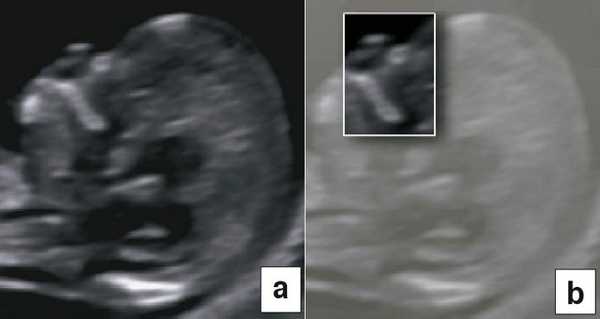

В начале 90-х годов прошлого века в практику был внедрен метод измерения толщины воротникового пространства (ТВП) в I триместре беременности, и к настоящему времени его считают показателем не только анеуплоидии, но и широкого спектра наследственных синдромов и пороков развития [2]. K. Николаидес (K. Nicolaides) с группой исследователей предложили новую модель скрининга на анеуплоидию и установили правила использования этого метода, в частности необходимость применения кривой обучения, проведения аудита, качественного (процедура оценки качества изображений) и количественного (медиана, дельты-ТВП и т.д.). Фонд медицины плода (Fetal Medicine Foundation) стандартизировал предложенный ими клинический протокол и установил правила сертификации для повышения качества медицинской помощи и уменьшения изменчивости результатов данных скрининга [3, 4]. Измерение ТВП можно проводить вручную (рис. 2a) или полуавтоматически (рис. 2b), чтобы результаты измерений были более воспроизводимыми. Кроме того, компания Samsung разработала дополнительный метод измерения показателей ТВП - 5D NT, позволяющий точно выявить срединно-сагиттальную плоскость и улучшить оценки по шкале Германа (Herman score).

Рис. 4. Диагностика хориальности и количества амнионов в I триместре путем оценки лямбда-признака (a) и T-признака (b).